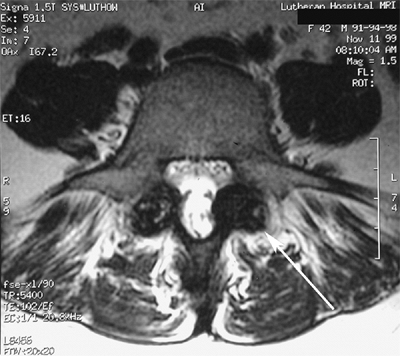

![]() |

Figure 21.7 Parasagittal reconstructed magnetic resonance imaging (MRI) view of lytic spondylolysis at L-5.

Figure 21.8 Axial magnetic resonance imaging (MRI) of bilateral pars interarticularis overgrowth (arrow) with foraminal narrowing.

|